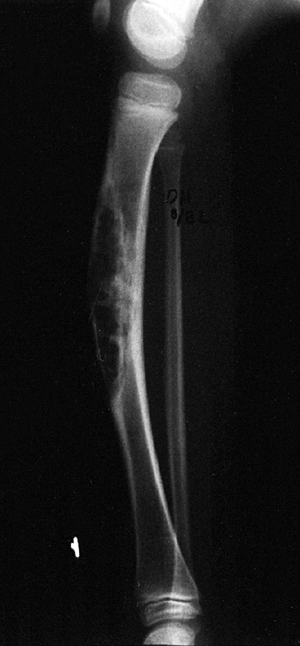

a bone or soft tissue mass includes neoplasia, infection, and trauma.

musculoskeletal tumor can be grave (Fig. 14.1).

Figure 14.1

Anteroposterior radiograph of the knee of a young man who complained of it “giving way.” The orthopaedist who saw the patient suspected a derangement, and the patient eventually had arthroscopic surgery. A radiolucent lesion can easily be seen in the lateral aspect of the proximal tibial metaphysis and epiphysis. This giant cell tumor of bone was missed because the physician did not consider this diagnosis when he was examining the patient or the radiograph. By the time the tumor was recognized, it had grown so large that resection and allograft reconstruction were required. Had it been treated when this radiograph was taken, a curettage and bone graft packing, or polymethyl methacrylate packing, could probably have been done. |